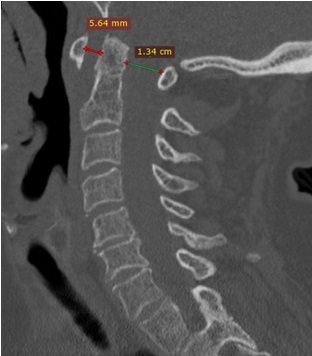

On May 2019 our patient was still complaining of severe cervical pain. Etanercept was stopped and Adalimumab 40 mg every two weeks was started. After one-month, cervical pain had significantly decreased and one month later it had completely remitted, with gain in bilateral cervical rotation (80°) and normalization of ESR and PCR.A follow up MRI was performed six months after starting adalimumab therapy and showed bone marrow edema disappearance from the odontoid process with normal signal intensity in STIR weighted sequence (Figure 3). On September 2020 our patient is still on Adalimumab therapy and persistent clinical remission.

Figure 3: MRI of cervical spine with sagittal acquisition six months after switching to adalimumab. STIR sequences show normal intensity signal of the odontoid process with complete regression of bone marrow edema of the dens.